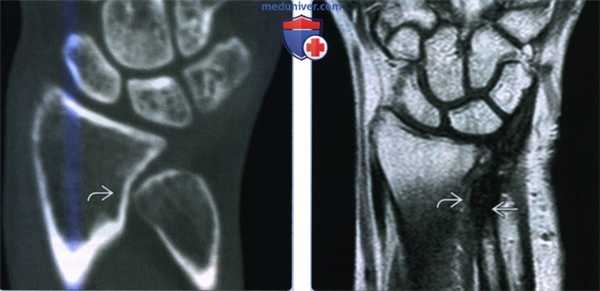

(Слева) На фронтальной КТ с реформатированием определяется лучелоктевой псевдоартроз с ремоделированием кортикального слоя лучевой кости. Имеется минимальный субкортикальный склероз, который является поздней находкой. Пациент жаловался на сильную боль при повторяющейся супинации.

(Справа) На фронтальной МРТ Т2ВИ определяется минимальная механическая эрозия дистального эпиметафиза лучевой кости у пациента, которому была проведена резекция дистального эпиметафиза локтевой кости (операция Дарраха) при лечении неутихающей боли в результате лучелоктевой нестабильности.